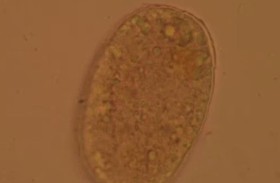

أطباء يصورون ديداناً مصاصة للدماء في أمعاء امرأة

أظهرت صور لحظة اكتشاف الأطباء لديدان تمتص الدماء تتلوى في أمعاء امرأة صينية، وكانت المزارعة البالغة من العمر 75 عاماً تعاني من مشاكل النوم وضعف الشهية والدوار لمدة شهرين قبل أن تسعى ... إقرأ المزيد